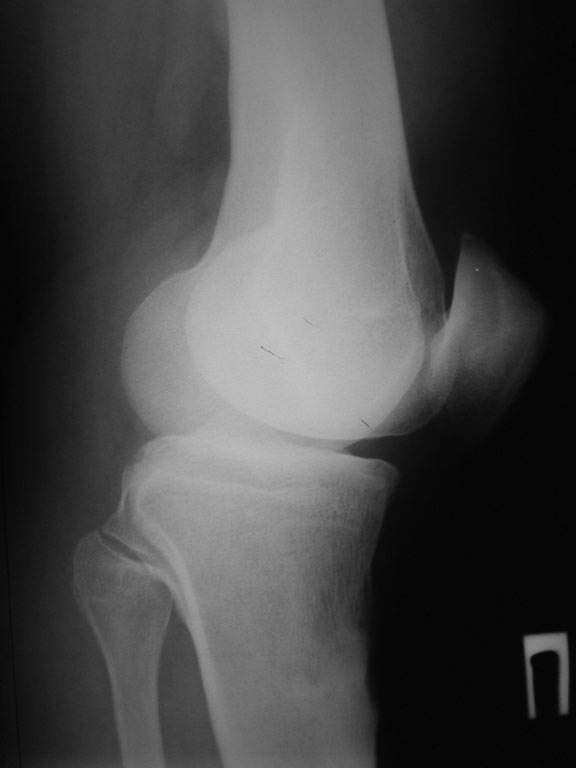

пациент наконец то объявился вновь и мы смогли выполнить новые снимки как лежа так и в нагрузке